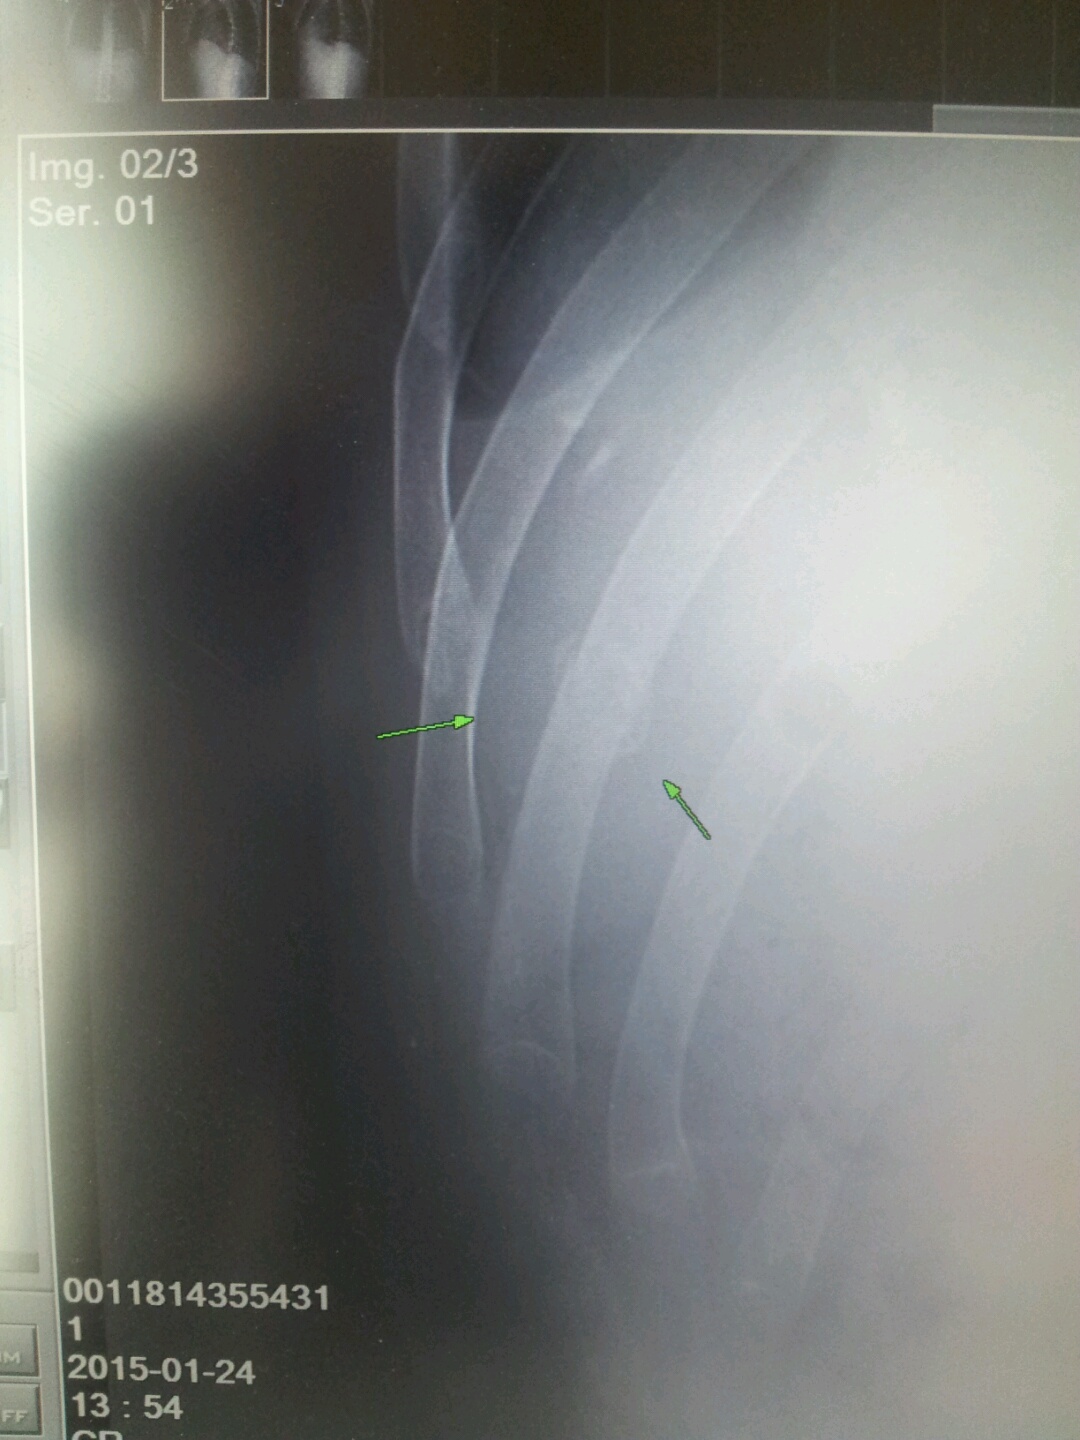

KakaoTalk_20151124_083649505.jpg

123413241324.jpg

작년 시즌 갈비뼈 하나가 부러진 상태로 3주간 부러진지도 모르고 탔습니다..ㅎㅎ

우연히 다른부위 엑스레이를 찍다가 갈비뼈가 살짝 어긋난 상태로 50%정도 붙어서 진액이 나온걸 발견한적 있네요ㅎㅎ

저번 시즌초엔 왼쪽 팔도 골절도 있었는데 부러진 다음날부터 일주일 통깁스 일주일 반깁스 한채로 그냥 시즌끝까지 계속 탔습니다.

저도 팔부러졌을땐 3개월, 갈비뼈는 부러진지 이미 3주가 이미 지났고 앞으로 더 3주 쉬라고  의사가 얘기했었는데, 탔어요..ㅎ